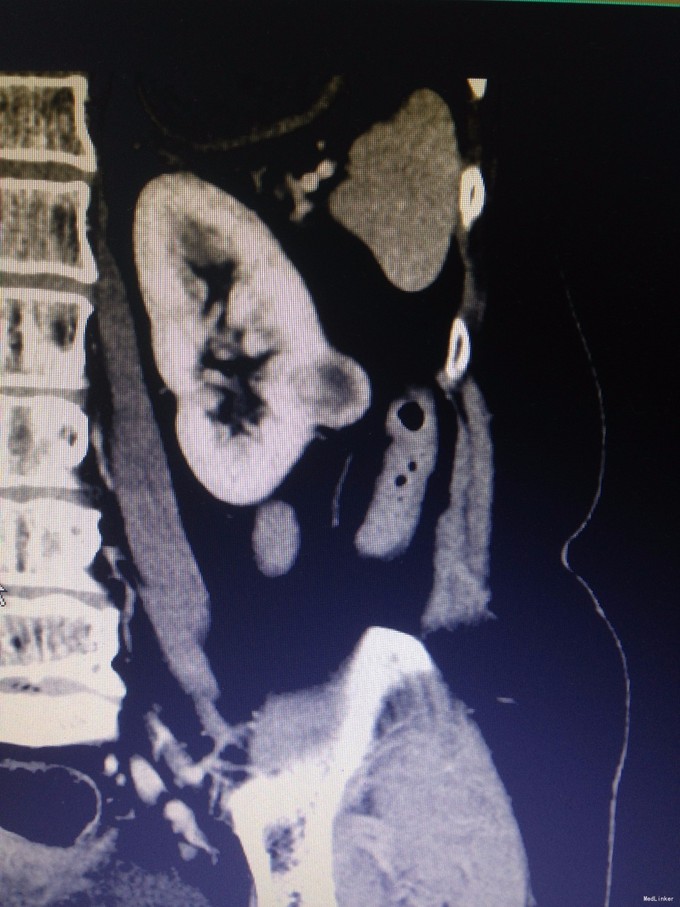

主诉:左腰部隐痛1月余 病史:患者老年女性, 61岁,1月余前无明显诱因出现左腰部隐痛,伴轻微酸胀感,无其他不适,未予就诊。1周前突发头晕、头胀痛感,至当地医院测血压得180/110mmhg。行腹部CT检查提示:左肾占位,肾癌可能性大。脂肪肝,腹主动脉钙化灶。予降压药物治疗后血压得以控制。现为进一步诊治收入我科。既往高血压病史5年,规律服药,血压控制良好。母亲因牙髓癌去世。

查体:腹部平软,无压痛反跳痛,双肾区无叩痛。 辅查:腹部CT提示:左肾占位,肾癌可能性大。脂肪肝,腹主动脉钙化灶。

诊断:左肾癌 治疗:完善术前准备后,行腹腔镜下左肾部分切除术,术程顺利,术后恢复良好。病理结果未回报。